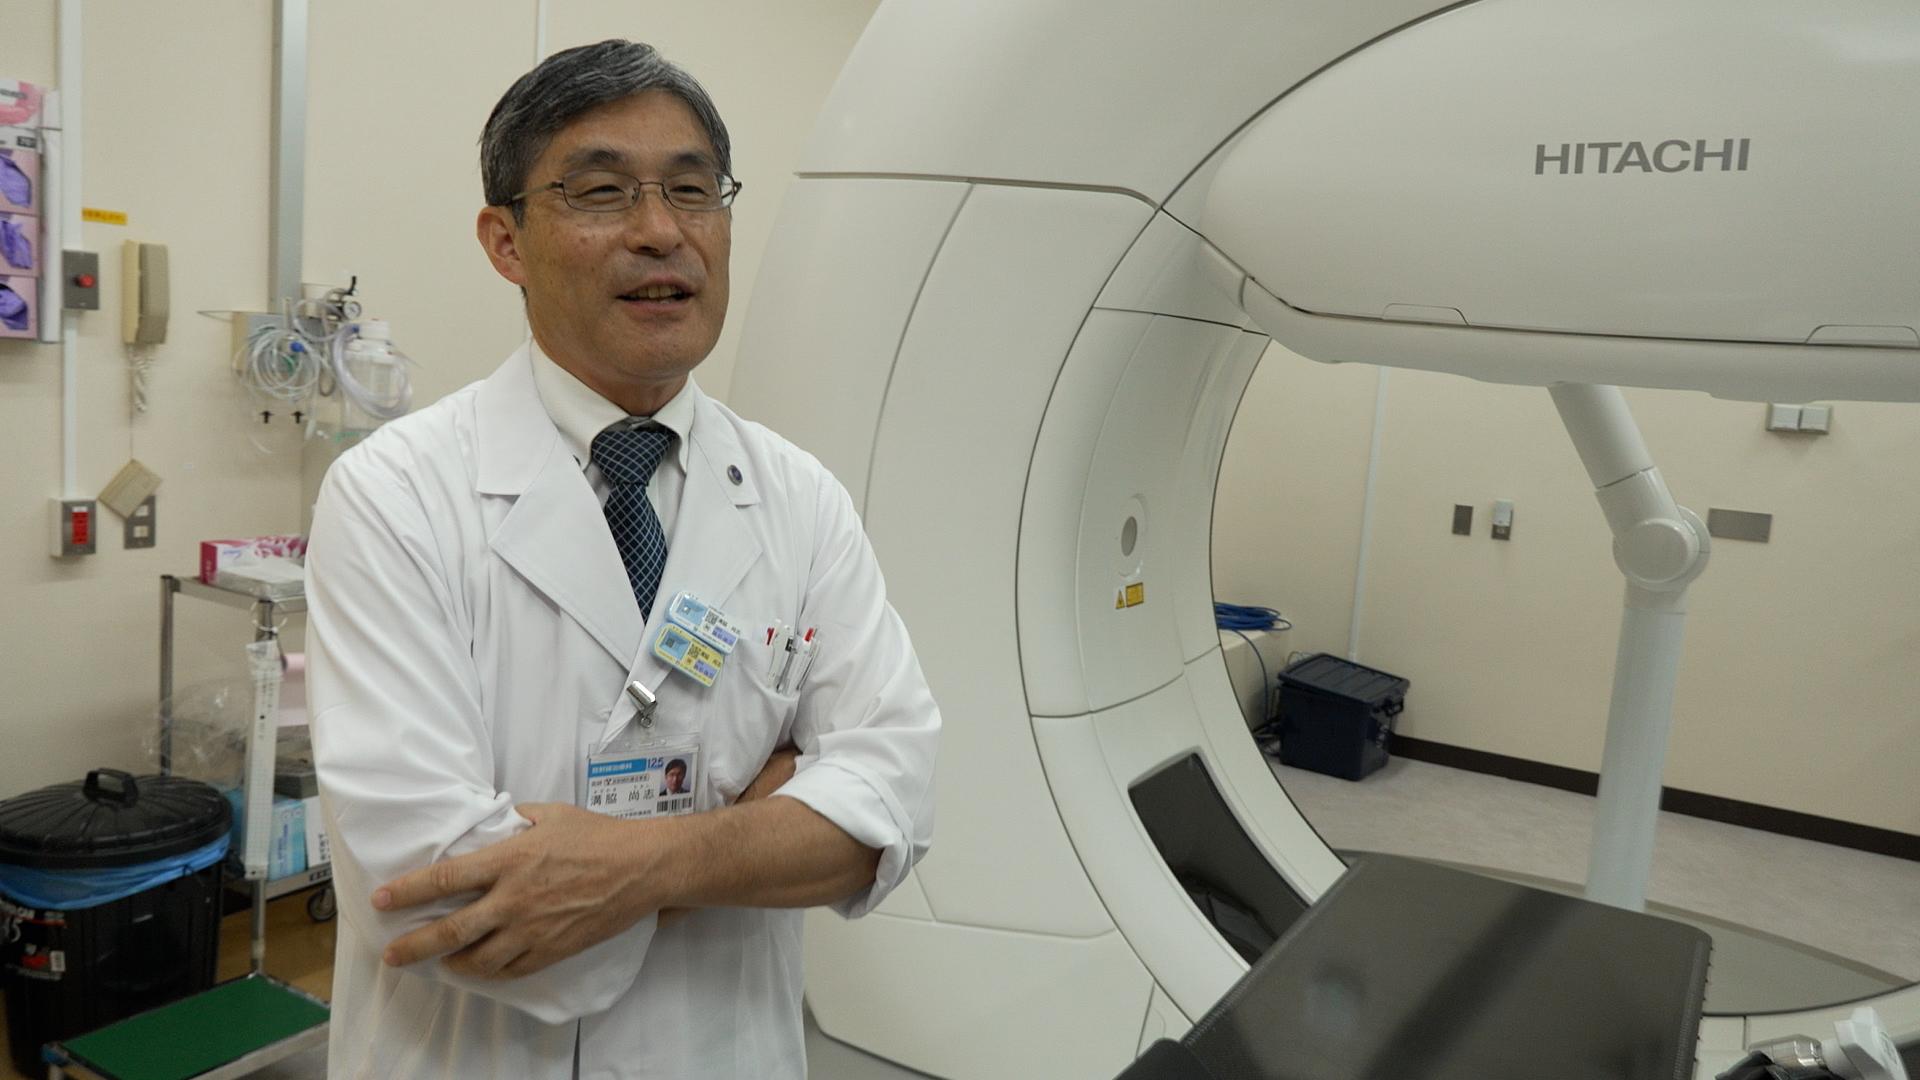

その放射線治療は、AIの進化などによる技術革新で、今後さらに治療の精度が上がることが期待されている。しかし、国内メーカーは装置の製造から相次ぎ撤退し、医療現場では海外メーカー製がシェアをほぼ独占する状態になっていた。ガイアは、進化する癌の高精度放射線治療の最前線を取材。これまでにない最新鋭の性能を武器に“悲願の国産装置”を開発した「日立ハイテク」と医師たちの挑戦を追う。